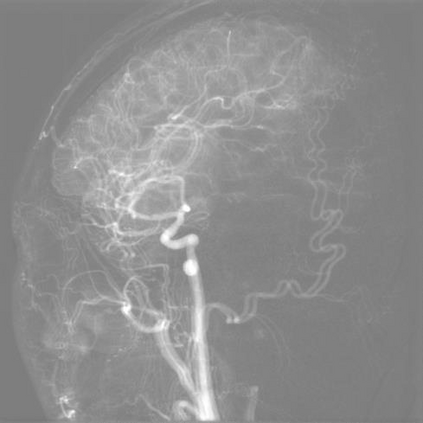

The rapid and accurate direct multi-frame interpolation method for Digital Subtraction Angiography (DSA) images is crucial for reducing radiation and providing real-time assistance to physicians for precise diagnostics and treatment. DSA images contain complex vascular structures and various motions. Applying natural scene Video Frame Interpolation (VFI) methods results in motion artifacts, structural dissipation, and blurriness. Recently, MoSt-DSA has specifically addressed these issues for the first time and achieved SOTA results. However, MoSt-DSA's focus on real-time performance leads to insufficient suppression of high-frequency noise and incomplete filtering of low-frequency noise in the generated images. To address these issues within the same computational time scale, we propose GaraMoSt. Specifically, we optimize the network pipeline with a parallel design and propose a module named MG-MSFE. MG-MSFE extracts frame-relative motion and structural features at various granularities in a fully convolutional parallel manner and supports independent, flexible adjustment of context-aware granularity at different scales, thus enhancing computational efficiency and accuracy. Extensive experiments demonstrate that GaraMoSt achieves the SOTA performance in accuracy, robustness, visual effects, and noise suppression, comprehensively surpassing MoSt-DSA and other natural scene VFI methods. The code and models are available at https://github.com/ZyoungXu/GaraMoSt.